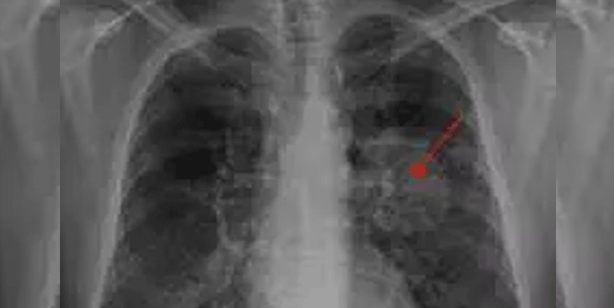

Yapılan incelemeler sonucunda, Xu'nun sağ akciğerinde yaklaşık 1 santimetrelik kitle fark eden doktorlar, bunun kötü huylu tümör olabileceği ihtimali üzerinde durdu.

Doktorlar, kanser olabileceği düşündükleri Xu'ya tam teşhis koyabilmek için akciğer dokusundan parça alarak testler yaptı. Yapılan testler sonucu, doktorların kötü huylu tümör sandığı kitlenin acı biber parçası olduğu anlaşıldı.

Biber parçasının, 2 yıl önce yemek yediği sırada boğazına kaçtığını ve şiddetli şekilde öksürdüğünü hatırlayan Xu'nun yaşadıkları Çin'deki sosyal medya platformlarında oldukça ilgi çekti.